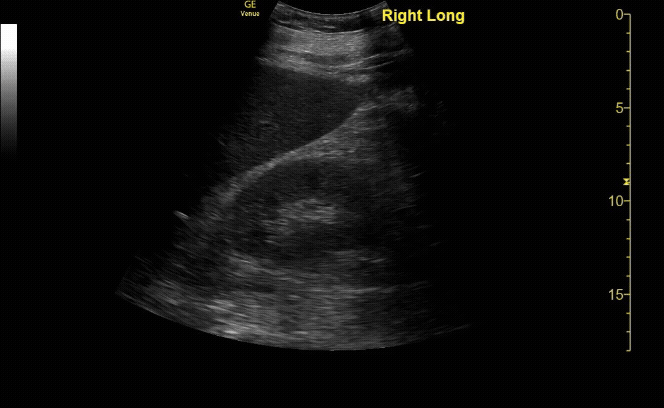

R/L kidney In sagittal (long) view

c/o Victoria Gonzalez, MD